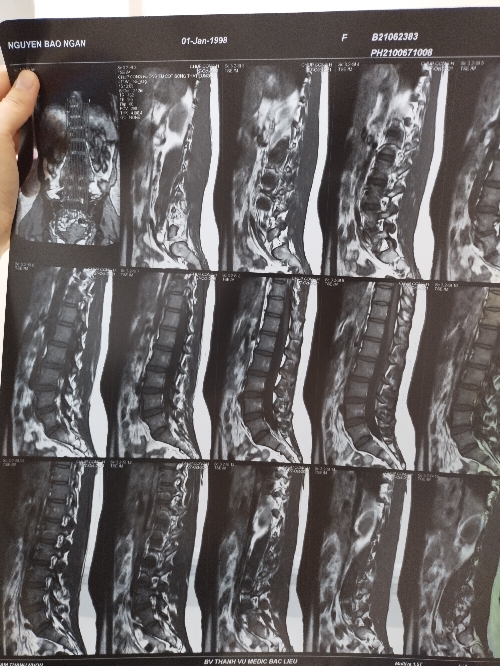

Thưa Bác Sĩ e hay bị đau xương mông với thắt lưng, e có đi chụp MRI mà bác sĩ xem kết quả nói e bình thường không bị sao rồi cho thuốc uống mà tới nay hơn tháng e vẫn còn bị đau ạ!